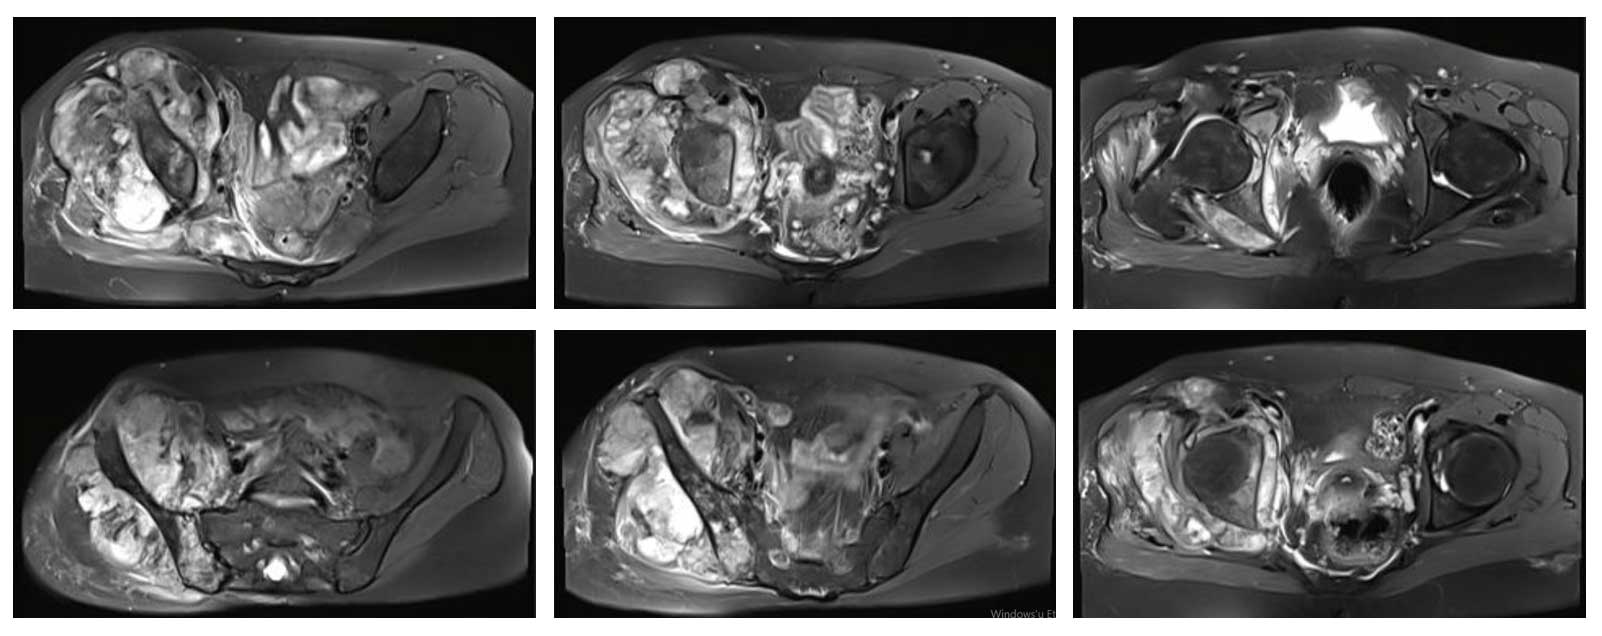

Ameliyat Öncesi: MR’da ek olarak yumuşak doku kitlesinin büyüklüğü, damar sinir paketine yakınlığı ve çevreleyen ödem görülmekte.